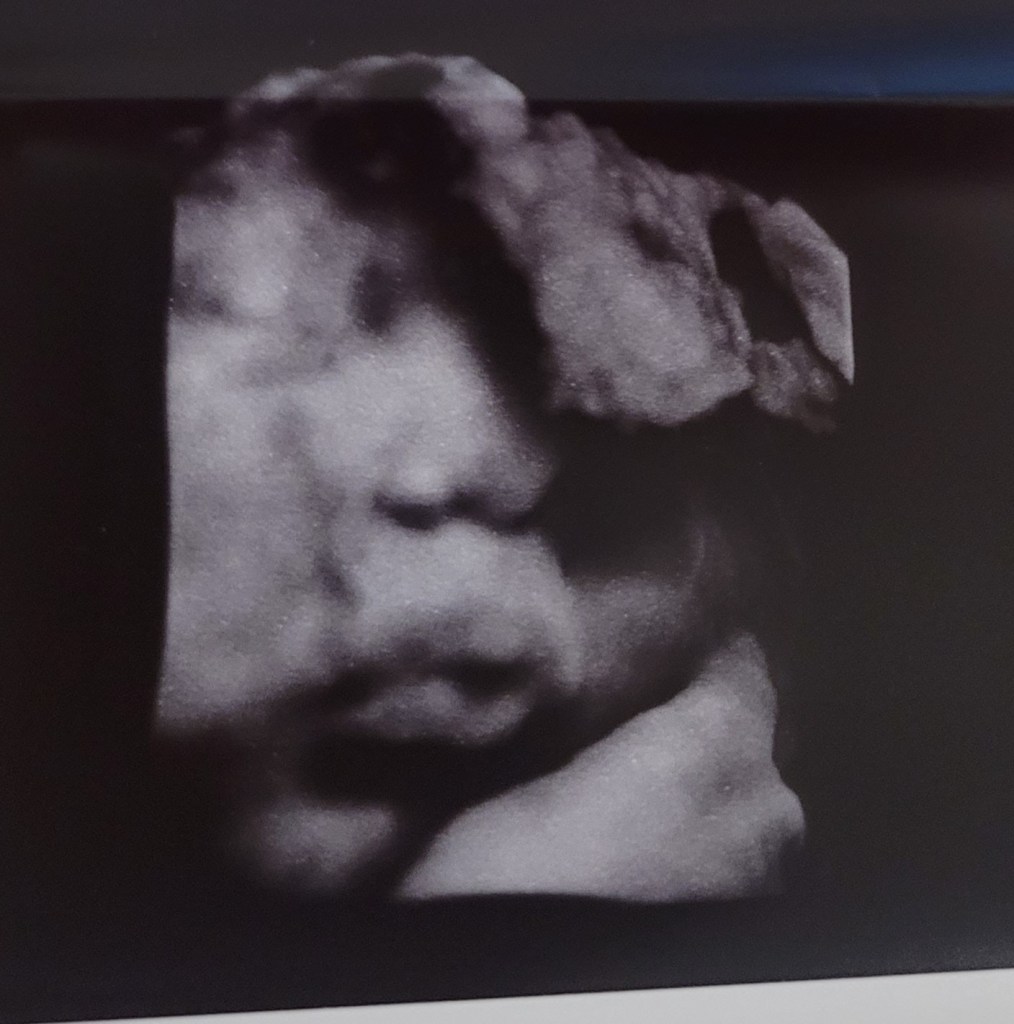

It was amazing to see the images they can get at a scan so late in the pregnancy, we could even see their hair moving in utero! I tried to pay attention to the percentiles and estimated weeks as I was particularly interested in how big this baby, that I was going to push out, was. Their head, measured in at 37 weeks and then they measured her belly. The weeks went past 40 and then changed to >99%. I noticed this but when her weight came in at 3.9kg I was distracted by that! If this baby went to term I would be giving birth to a 5kg baby!